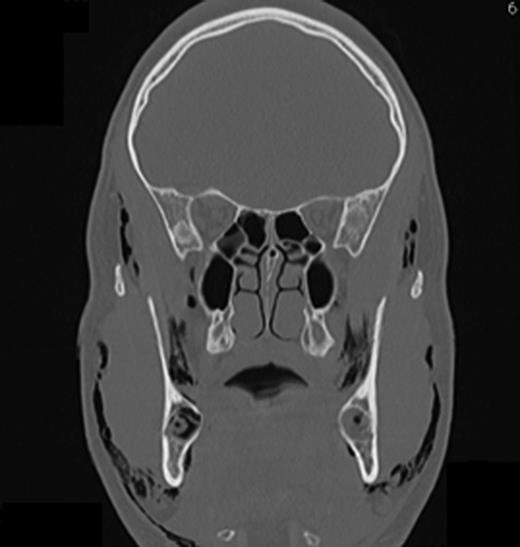

Computed tomography (CT) of the head and neck region revealed a bilaterally located subcutaneous air collection in the area of the periorbital, temporal, paramandibular and supraclavicular region (Figs 3–5). There were no signs or symptoms of severe complications such as pneumothorax or pneumomediastinum.

The frontal CT scan of the head and neck region (section in the retromolar region) illustrates bilaterally trapped air into the soft tissue reaching from the temporal fascia through to the supraclavicular region.